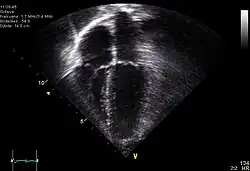

| Diagnostic method | ECG, chest x-ray, bedside echocardiogram |

Diagnosis of traumatic cardiac arrest is initially made with electrocardiogram with EMS or in the emergency department. Clinicians will also order diagnostic testing that may include chest x-ray, bedside ultrasound and echocardiogram, and blood gas levels. A type and cross will be ordered to match the patient to receive blood transfusion if necessary.

Other work-up involved in diagnosis of a trauma patient may include e-FAST, RUSH exam, CBC, pelvic X-ray, and CT of the head, neck, chest, abdomen, and pelvis.